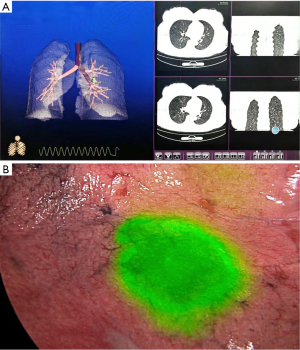

ENB-guided localization with ICG

All ENB procedures were performed in the operating room utilizing the LungCare navigation system (LungCare Medical Technologies Ltd., Inc., Suzhou, China). Preoperative planning included acquisition of high-resolution chest CT scans with 1-mm slice thickness, followed by three-dimensional virtual pathway reconstruction to the target lesion using dedicated software. Following induction of general anesthesia with single-lumen endotracheal intubation, standard bronchoscopic examination was performed, with the bronchoscope maintained at the carina during insertion of the locatable guidewire within its guiding sheath. Registration was completed through sequential advancement of the bronchoscope into both main bronchi and subsequent withdrawal to the trachea. Successful registration required ≥80% matching accuracy between real-time and virtual images. After observing three complete respiratory cycles to minimize registration artifacts, the operator navigated the bronchoscope to the target bronchus using multiplanar reconstructed images for guidance. Upon confirmation of target lesion accessibility through concordance of real-time and virtual images, the locatable wire was withdrawn and 2.3 mL of indocyanine green (ICG; 25 mg, Dandong Yichuang Pharmaceutical Co., Ltd., China) was injected for marking, with 0.3 mL delivered to the target site and 2.0 mL retained within the sheath (Figure 4). Procedural success was defined as the surgical team’s ability to rapidly identify and resect the nodule from the marked location during subsequent surgery, while failure was characterized by inability to achieve these objectives. All ENB localization procedures were performed by certified interventional pulmonologists with specialized training in navigational bronchoscopy techniques.